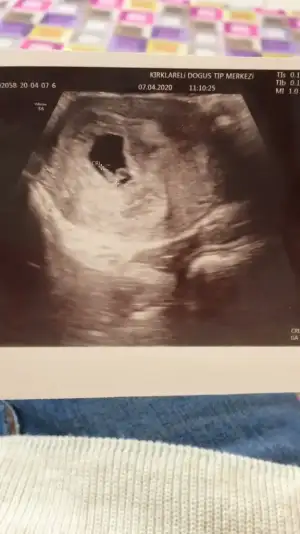

Benim 7 haftalık☺️Yorum yaparsanız sevinirim🥰